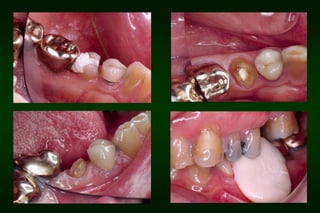

Requirements of Provisional Restoration I. Biologicrequirement: • • • • • Protect the dental pulp Maintain and contribute to the periodontal health Provide comfortable, functional occlusal relationship Maintain tooth position Protect remaining tooth structure

After 1 week

After 2 months